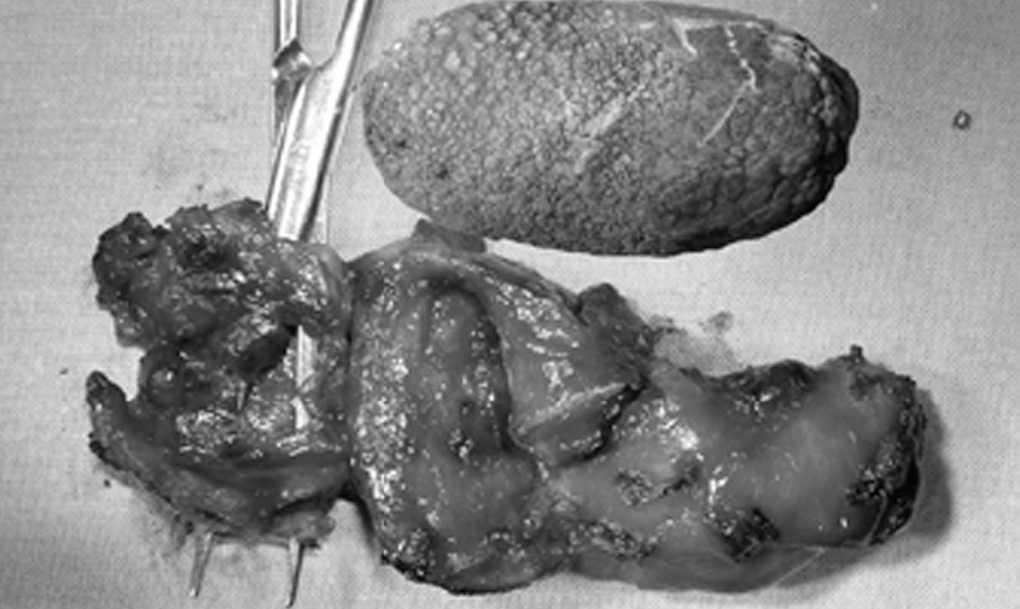

Mujer de 76 años que ingresa por cuadro clinicoanalítico de ictericia obstructiva de 15 días de evolución y fiebre > 38 °C en las últimas 48 h. Una colangiorresonancia magnética (fig. 1) evidencia un único cálculo vesicular que ocupa toda la vesícula, que comprime y obstruye el colédoco, y dilata la vía biliar. Intraoperatoriamente se comprueba una colelitiasis única de 5 x 3 cm enclavada en la porción infundibular de la vesícula, lo que da lugar a una fístula por decúbito colecistocoledociana con un orificio en el colédoco en su tercio medio de 1,5 cm (fig. 2). Se realiza colecistectomía, resección de 2,5 cm del colédoco y hepaticoyeyunostomía en "Y" de Roux.

Fig. 2.

El síndrome de Mirizzi tipo 2 se produce como consecuencia del enclavamiento de un cálculo en el infundíbulo o conducto cístico, que erosiona la pared del colédoco y produce una fístula colecistocoledociana. Cuando existe una afección mayor del colédoco, se puede optar por la colecistectomía, la resección de colédoco y la hepaticoyeyunostomía en "Y" de Roux.